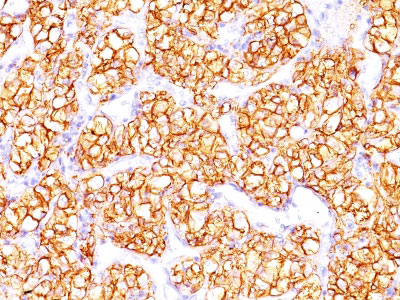

Formalin-fixed, paraffin-embedded human Renal Cell Carcinoma stained with PNA Monoclonal Antibody (PN-15). |

Recognizes a glycoprotein of ~200kDa, identified as carbonic anhydrase IX (CAIX/gp200). Its epitope resides in the carbohydrate domain of gp200. It shows no significant cross-reactivity with other carbohydrate determinants, such as the Lewis blood group antigens, epithelial membrane antigen, HMFG, and AB blood group antigens. In normal kidney, gp200 is localized along the brush border of the pars convoluta and pars recta segments of the proximal tubule, as well as focally along the luminal surface of Bowman's capsule adjoining the outgoing proximal tubule. Reportedly, gp200 is expressed by 93% of primary and 84% of metastatic renal cell carcinomas. This MAb may be useful in the investigations of carcinomas of proximal nephrogenic differentiation especially those showing tubular differentiation.